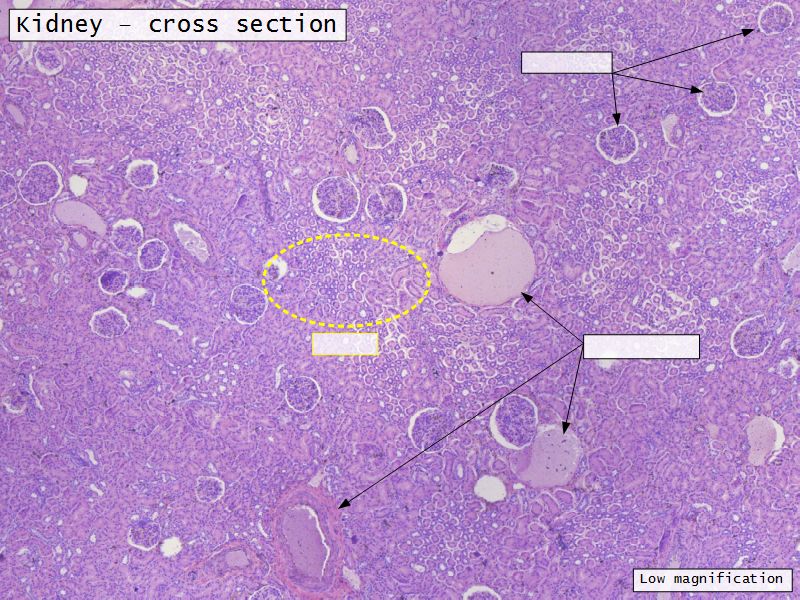

Appearance

- Cortex

- Renal corpuscles

- Convoluted tubules

- Medulla

- Loops of Henle

- Collecting tubules

Kidney lobule

- Group of neprons

- Open into branches

- Same collecting duct

- Not clearly demarcated

- Interlobular arteries/veins